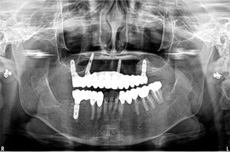

オールオン4の治療例:2

治療前

治療後